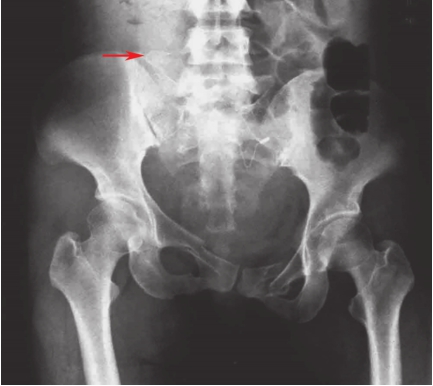

患者取仰卧位,射线倾斜45°指向头侧投射。可显示骶骨、骶孔、髂骨翼、髋臼和髂耻隆起的骨折。主要是判断半侧骨盆有无垂直移位、骶骨骨折;骨盆前环有无变宽和骨折等(图2-4)。

图2-4 骨盆出口位X线片

可见右侧骶骨骨折,提示后环损伤;L

5

横突骨折,提示骨盆骨折不稳,右半侧骨盆向上移。